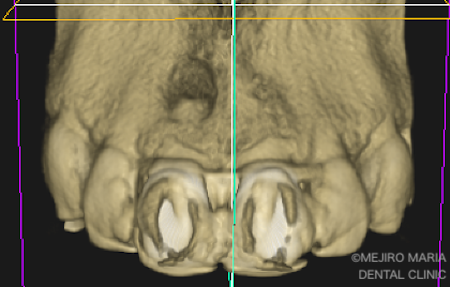

初診時にCT撮影を行い診査したところ、右上1番の根尖の骨は、根尖性歯周炎により喪失していました。また、左上1番の歯にも小さい病変(根尖性歯周炎)が確認されました(2枚目の写真)。